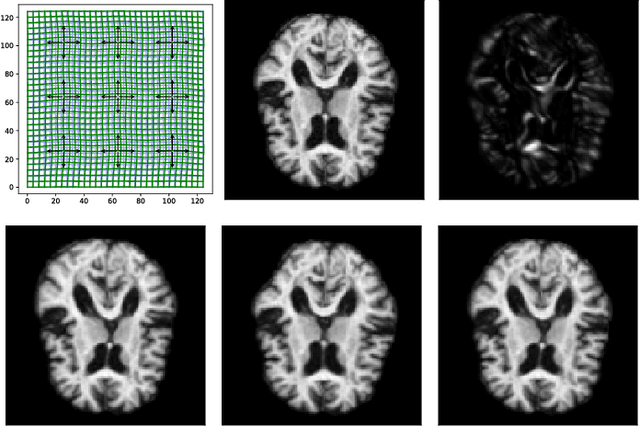

Abstract:Modelling deformation of anatomical objects observed in medical images can help describe disease progression patterns and variations in anatomy across populations. We apply a stochastic generalisation of the Large Deformation Diffeomorphic Metric Mapping (LDDMM) framework to model differences in the evolution of anatomical objects detected in populations of image data. The computational challenges that are prevalent even in the deterministic LDDMM setting are handled by extending the FLASH LDDMM representation to the stochastic setting keeping a finite discretisation of the infinite dimensional space of image deformations. In this computationally efficient setting, we perform estimation to infer parameters for noise correlations and local variability in datasets of images. Fundamental for the optimisation procedure is using the finite dimensional Fourier representation to derive approximations of the evolution of moments for the stochastic warps. Particularly, the first moment allows us to infer deformation mean trajectories. The second moment encodes variation around the mean, and thus provides information on the noise correlation. We show on simulated datasets of 2D MR brain images that the estimation algorithm can successfully recover parameters of the stochastic model.